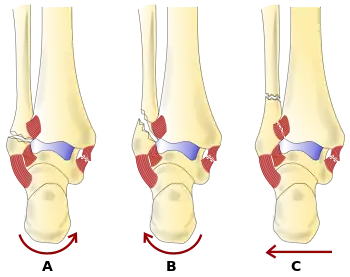

- The Lauge-Hansen classification categorizes fractures based on the mechanism of the injury as it relates to the position of the foot and the deforming force (most common type is supination-external rotation)

- The Danis-Weber classification categorizes ankle fractures by the level of the fracture of the distal fibula (type A = below the syndesmotic ligament, type B = at its level, type C = above the ligament), with use in assessing injury to the syndesmosis and the interosseous membrane